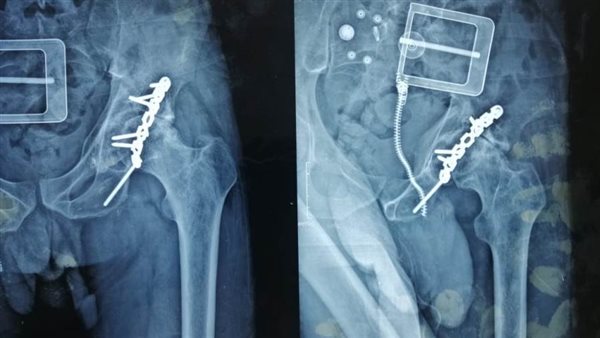

وكان المستشفى استقبل مريض يبلغ من العمر 30 عاما، ويعاني من كسر قديم في حق مفصل الحوض مثبت سابقا بشريحة ومسامير، مع وجود إصابة جزئية في العصب الوركي منذ أكثر من خمس أعوام أدت إلى خشونة حادة و تآكل في مفصل الفخذ، مع وجود عرج واضح بالمشي.

وتم وضع المريض ضمن الحالات الحرجة لقوائم الانتظار، حيث تمكن الفريق الطبي من إجراء استبدال مفصل فخذ صناعي كامل، واستغرقت العملية حوالي ثلاث ساعات، وتعد من الجراحات المتقدمة ذات المهارة الخاصة.